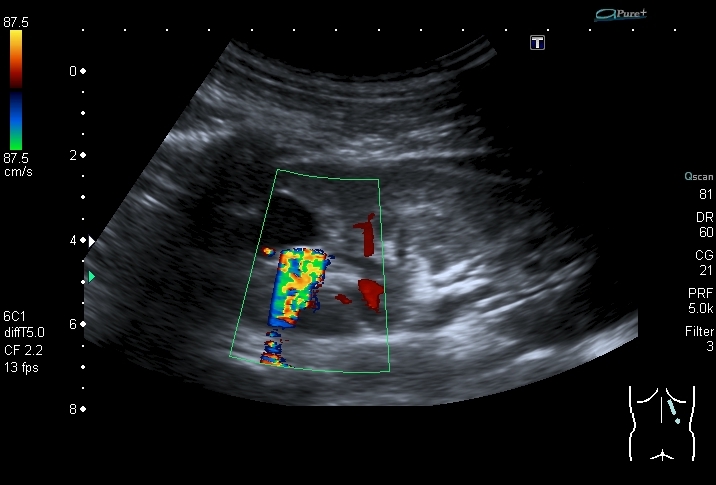

Конкременты в кисте почки.

Мальчик 14 лет, на плановой госпитализации, выставлен хронический пиелонефрит.

Артефакт цветного твинклинга

Скан области интереса

Ролик с ЦДК